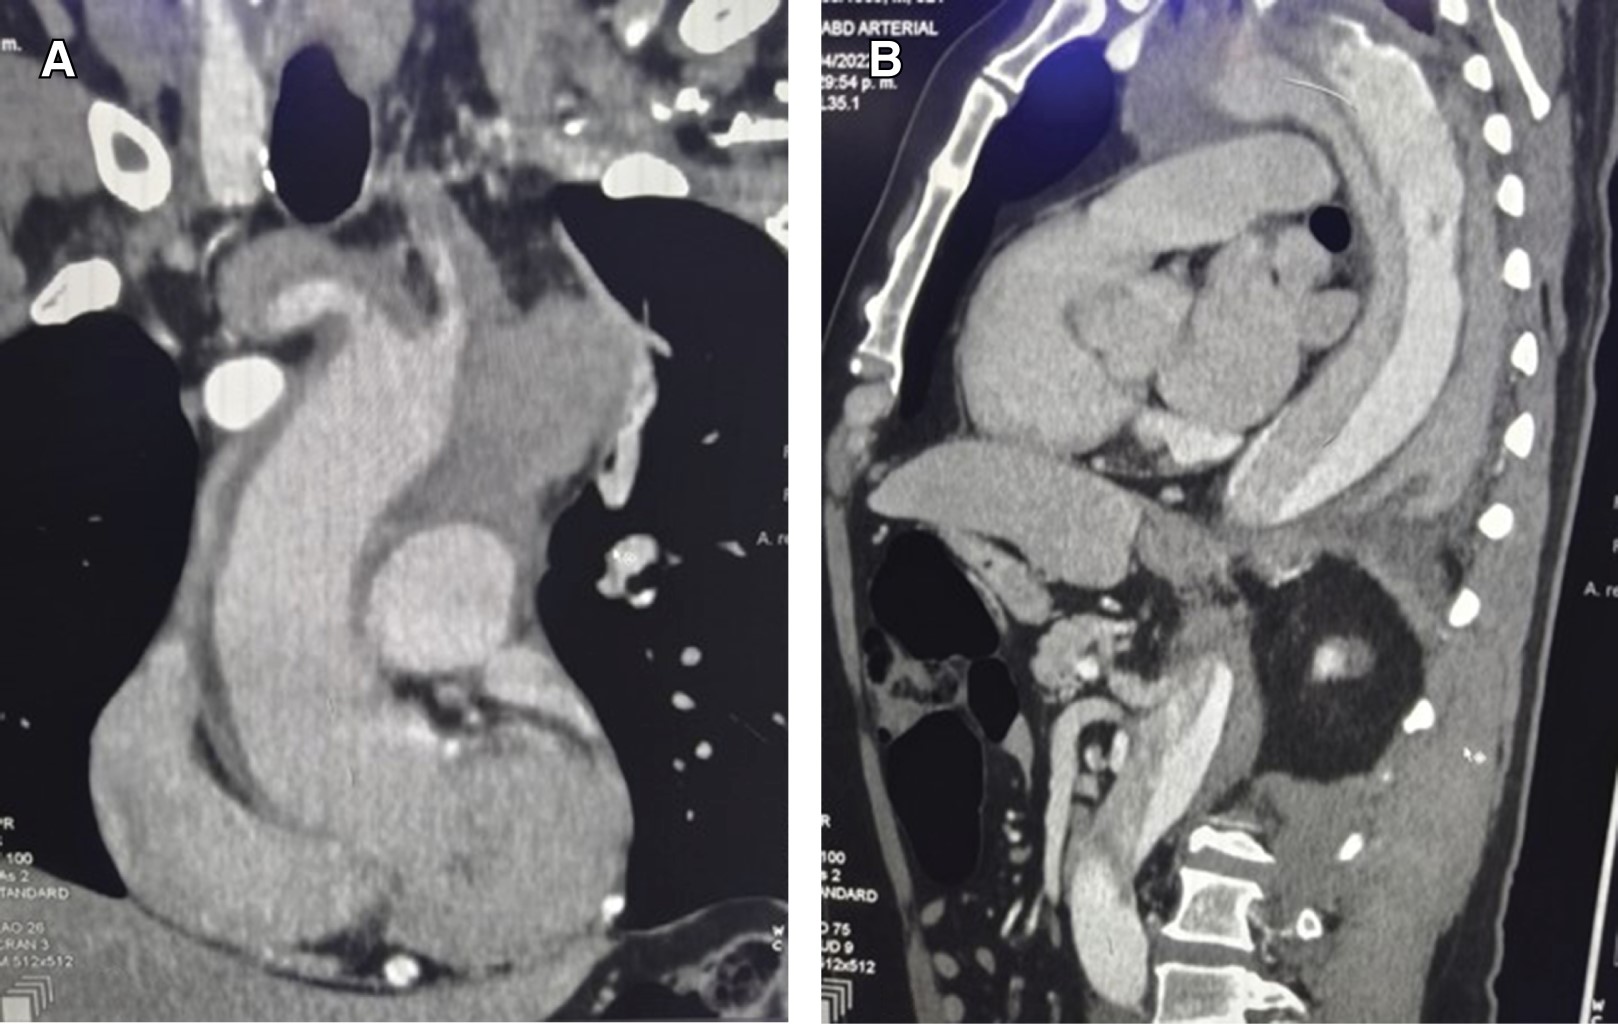

CT Angiography showed intramural hematoma that begins in the sinus of Valsalva and extends to the proximal arch, dissection flap that begins in the brachiocephalic trunk and extends to the right common carotid, proximal third of the left common carotid, and the subclavian artery and continues to the distal third of the left internal iliac artery, the right renal artery arises from the false lumen, the rest of the visceral branches emerge from the true lumen (Figure 1).

Figure 1